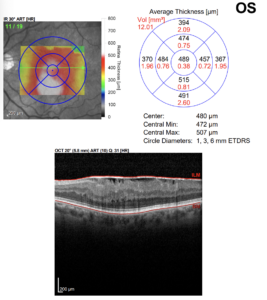

Tomografia de coerência óptica (OCT) macular – olho esquerdo: espessamento retiniano difuso com elevação e irregularidade da superfície interna (ILM), associado a tração e pregueamento das camadas internas, compatíveis com membrana epirretiniana. Observa-se padrão de desorganização das camadas internas da retina (DRIL) e perda da depressão foveal normal, com espessura central de 480 µm. Esses achados corroboram o diagnóstico clínico de pucker macular secundário à membrana epirretiniana.